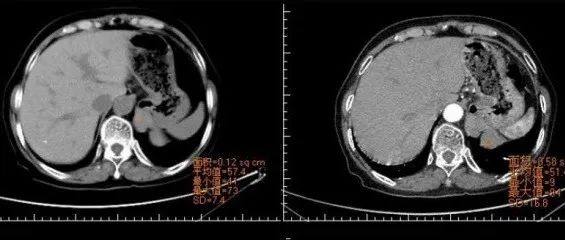

医学影像 yxyx-app 医学影像APP,打造伴随医生快速成长的影像学习社区。与影像园(Xctmr.com)一起提供最全面的影像案例库、基础(解剖、病理、影像诊断)知识、影像技术及考题等,为医生提供最佳的医学影像参考。【所属科室】呼吸科【基本资料】患者,女,20岁【主诉】干咳伴胸痛半月【影像图片】【讨论问题】如何诊断?【医学影像APP用户讨论】评论:左前纵隔见一囊样包块影,内见结节状、条片状脂性密度影,局部囊壁见壁结节影,增强见囊壁及壁结节明显均匀强化;上纵隔脂肪间隙密度增高,但与包块分界尚清,增强后内未见明显强化;肺动脉主干及左侧肺动脉见受压推移,未见充盈缺损影。前纵隔占位,考虑畸胎瘤。...